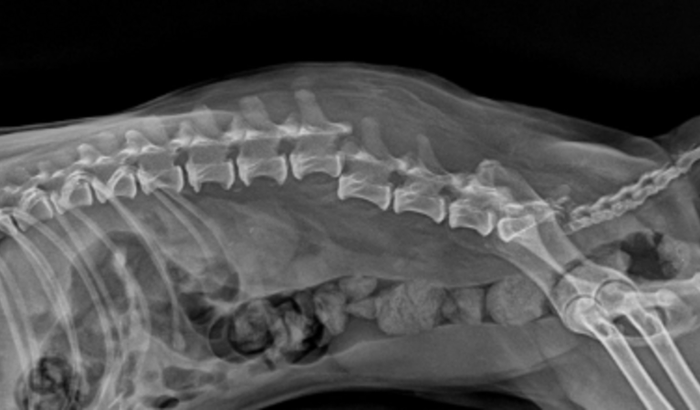

Oi, esta é a Amiguinha, nossa cachorrinha de 12 anos, ela já esta idosa e é ceguinha, infelizmente ela sofreu um acidente onde fraturou a coluna e perdeu os movimentos das patinhas traseiras, precisamos fazer esta cirurgia o mais rápido possível (ate quarta feira 19/02) na esperança dela voltar a andar. Peço ajuda de todos que puderem ajudar com qualquer valor, e quem puder compartilhar ja ajuda muito tambem. Estamos em uma corrida contra o tempo Por favor ajudem!